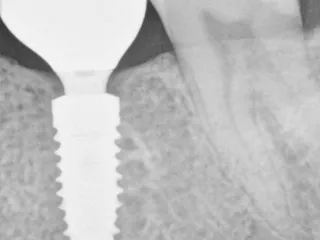

• Post insertion radiograph.